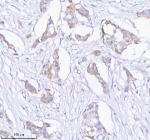

Immunohistochemical staining of SASS6 using anti-SASS6 antibody (red). SASS6 was detected in a paraffin-embedded section of human appendiceal carcinoid tissue. Heat mediated antigen retrieval was performed in EDTA buffer (pH 8.0, epitope retrieval solution). The tissue section was blocked with 10% goat serum. The tissue section was then incubated with 2 ug/ml rabbit anti-SASS6 antibody overnight at 4oC. Peroxidase Conjugated Goat Anti-rabbit IgG was used as secondary antibody and incubated for 30 minutes at 37oC. The tissue section was developed using an HRP secondary and DAB substrate.

Immunohistochemical staining of SASS6 using anti-SASS6 antibody. SASS6 was detected in a paraffin-embedded section of human appendiceal carcinoid tissue. Heat mediated antigen retrieval was performed in EDTA buffer (pH 8.0, epitope retrieval solution). The tissue section was blocked with 10% goat serum. The tissue section was then incubated with 2 ug/ml rabbit anti-SASS6 antibody overnight at 4oC. Peroxidase Conjugated Goat Anti-rabbit IgG was used as secondary antibody and incubated for 30 minutes at 37oC. The tissue section was developed using an HRP secondary and DAB substrate.